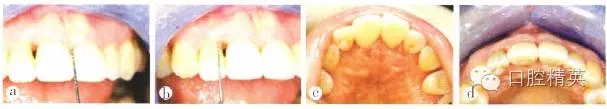

修復(fù)后2周復(fù)查,11間“黑三角”接近消失,鄰間隙關(guān)閉效果基本達到;到間唇側(cè)牙齦增厚,但仍有2~3 mm高的齦乳頭缺陷,繼續(xù)觀察其生長,并對患者進行定期牙周維護(圖8)。修復(fù)后1年復(fù)查,11間齦乳頭充盈良好,21間齦乳頭充盈程度改善,但尚未完全充滿,上前牙區(qū)唇側(cè)外形輪廓豐滿。患者微笑時,可見上前牙“黑三角”基本消失(圖9)。

a 11間“黑三角”接近消失;b 21間唇側(cè)牙齦增厚,但仍存在2-3mm高的齦乳頭缺陷;c 上前牙腭側(cè)觀;d 上前牙牙合面觀

圖8 修復(fù)后2周復(fù)查

a上前牙區(qū)正面觀,11間齦乳頭充盈良好,21間齦乳頭充盈程度改善,但尚未完全充滿;b上前牙區(qū)牙合面觀,唇側(cè)外形輪廓豐滿:c上前牙區(qū)腭側(cè)觀;d患者微笑像.“黑三角”基本消失;e上前牙區(qū)側(cè)面觀

圖9 修復(fù)后1年復(fù)查